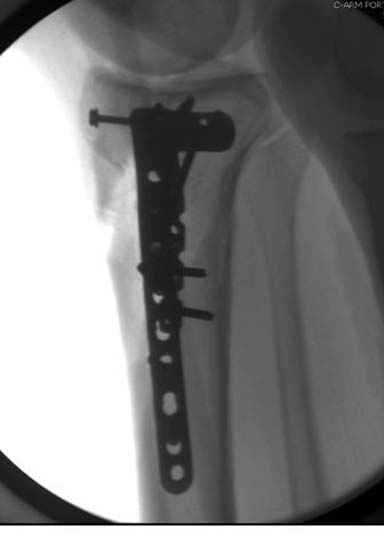

При переломах одного из мыщелков тибиал плато+дополнительный перелом проксимальной трети большеберцовой кости можно применить комбинированный вариант фиксации, т.е. мыщелок винтами или пластиной, а для диафиза можно установить гвоздь. В данном варианте потеряно преимущество гвоздя , из-за серьезной травмы суставной поверхности нельзя нагружать ногу несколько месяцев. А без нагрузки гвоздь просто заполнитель пространства внутри кости!

На вашем место я бы подождал с фиксацией до готовности кожных покровов, и за это время можно было подобрать соответствующий фиксатор, т.е более длинная пластина снаружи и медиальная пластина на апексе перелома как подпорка. Здесь приемлем как раз минимальный доступ.

Здесь пару случаев для сравнения,...в первых 1-4 слайдах метод фиксации одним фиксатором, как видно после 8 месяцев сохранилась ось. С 5 по 9 вариант двумя пластинами...